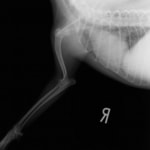

症例:柴犬 3歳

左後肢の完全挙上を主訴に来院されました。触診にて近位足根関節の過伸展を、レントゲン検査にて左足根関節周囲の軟部組織の腫脹、ストレス撮影によって距骨・踵骨と第4足根骨・中心足根骨間の脱臼および過伸展を認めました。

術前側面像屈曲位

術前側面像伸展位